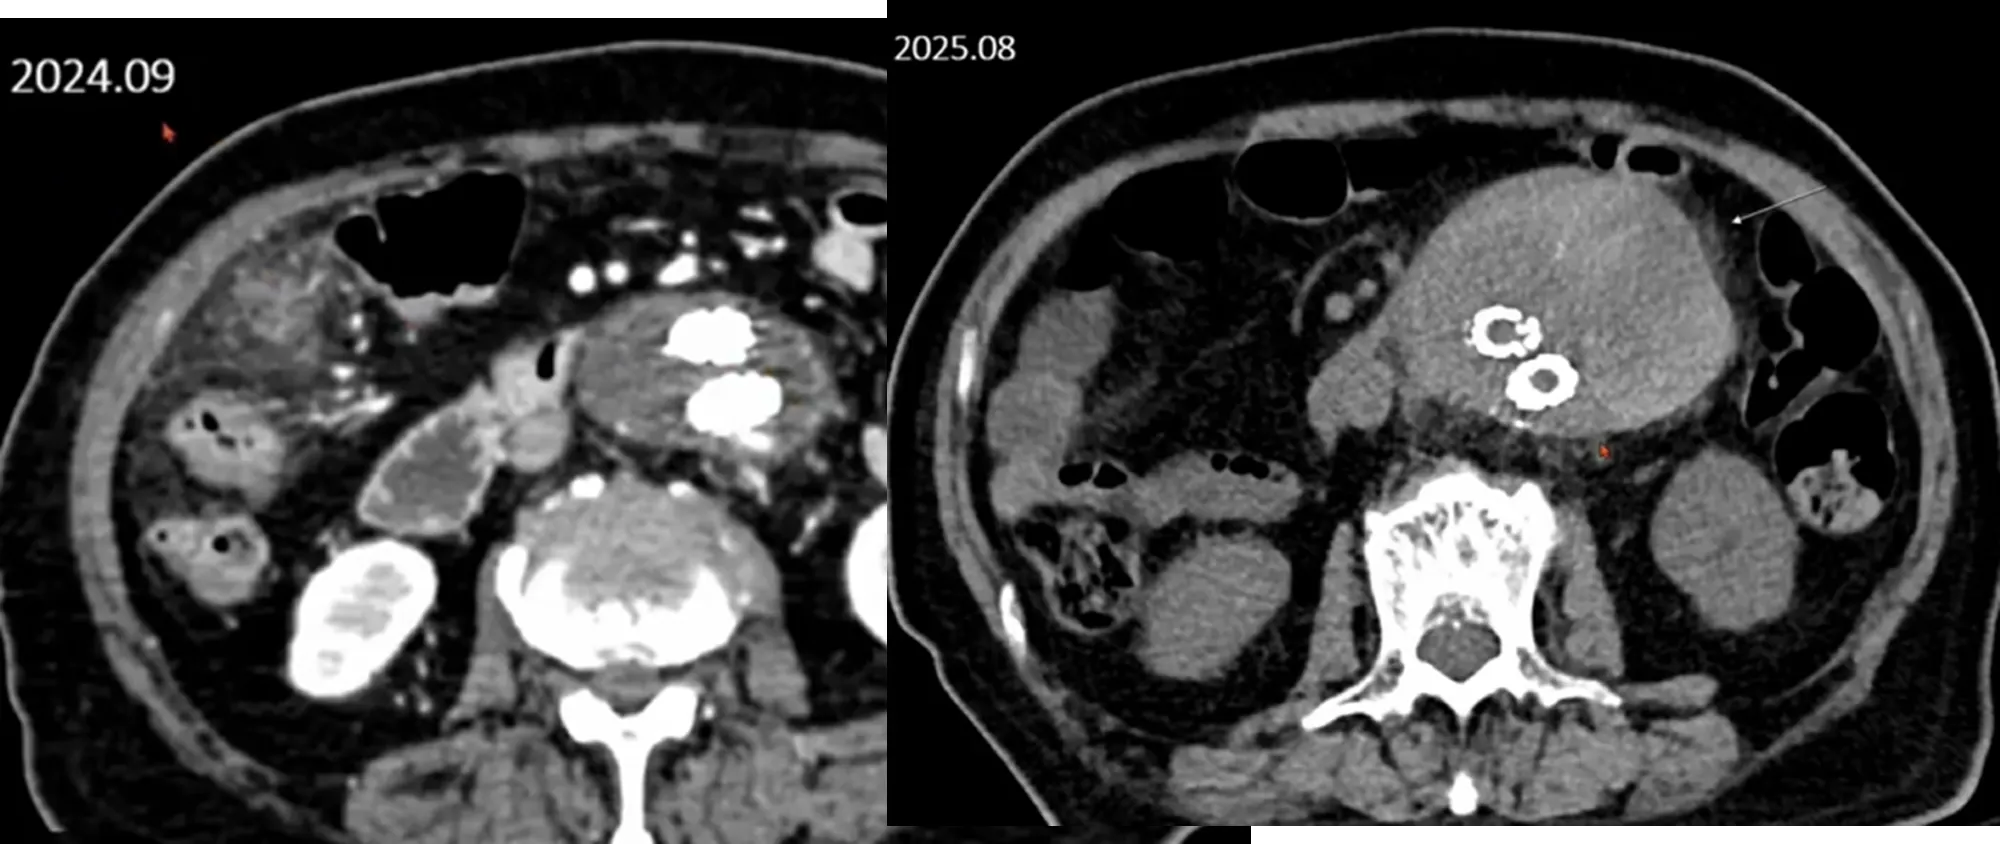

Case 10-1

•

M/94

C/C: abdominal pain

Hx : sigmoid colon cancer s/p anterior resection , AAA s/p EVAR, s/p PTGBD insertion

Lab: CRP 14.9mg/dL, Hb 9.6g/dL

Contained rupture

Case 10-2

M/43

C/C: Abdominal pain, aggravation

Hx : h/o ureter stone

Lab: within normal limit